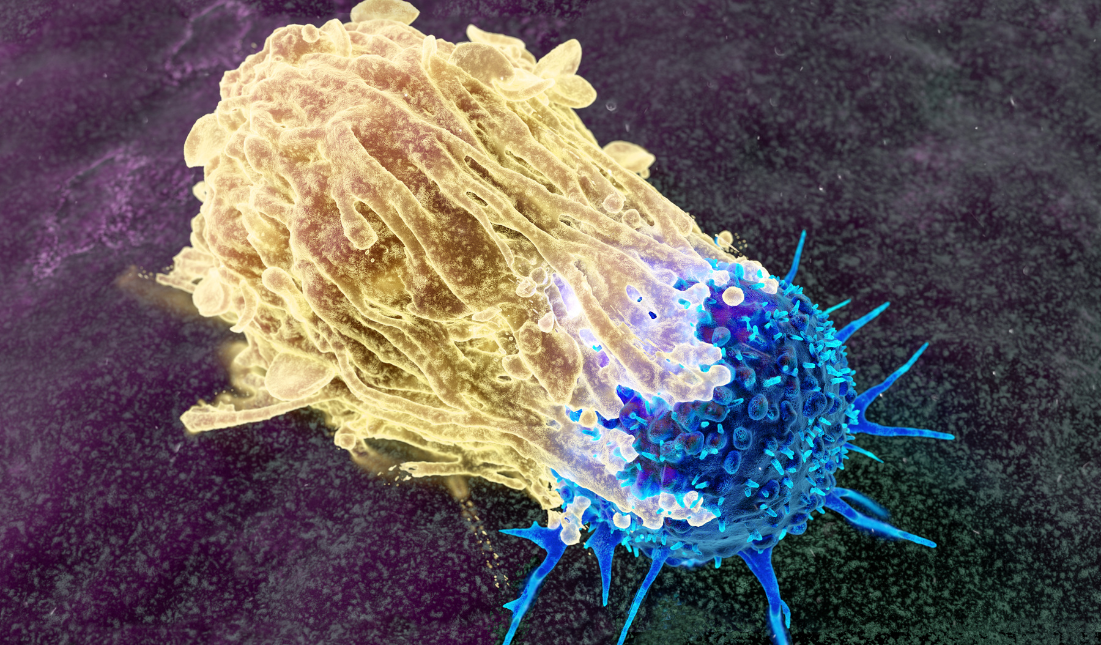

Read MoreCancer Vaccines

Home Cancer vaccines represent a promising frontier in medical science, designed to...